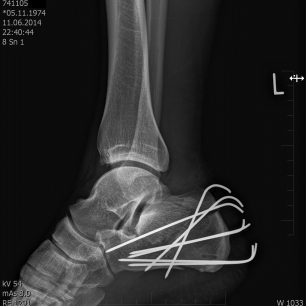

Ještě ten den večer jdu na sál. Zlaté ruce Fildy za hodinu spletli na mé patě ze sedmi drátů klec, něco jako když se o Velikonocích splétá pomlázka a uvěznili v něm ježka. Respektive myšlenku mi vnukl až pohled přes rameno na rentgenový snímek s daným výtvorem a samolibě spokojeného umělce. Celý akt té řezničiny byl zakončen hlubokým hlasem Alfa samce s rouškou na tváři, v podobě pochvalné ódy na sebe sama a slovy, „Fakt se mi to povedlo.“